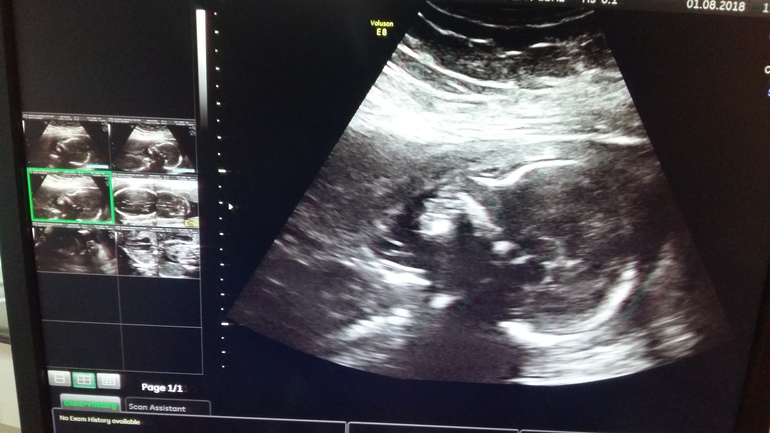

Добрый вечер!Сходили мы сегодня на узи-скрининг.Тфу-тфу-тфу все хорошо.развиваемся по сроку.Интрига раскрыта))У нас будет еще одна принцесса!!!Ура!!!Вес 334гр срок на момент узи 20.1нед.